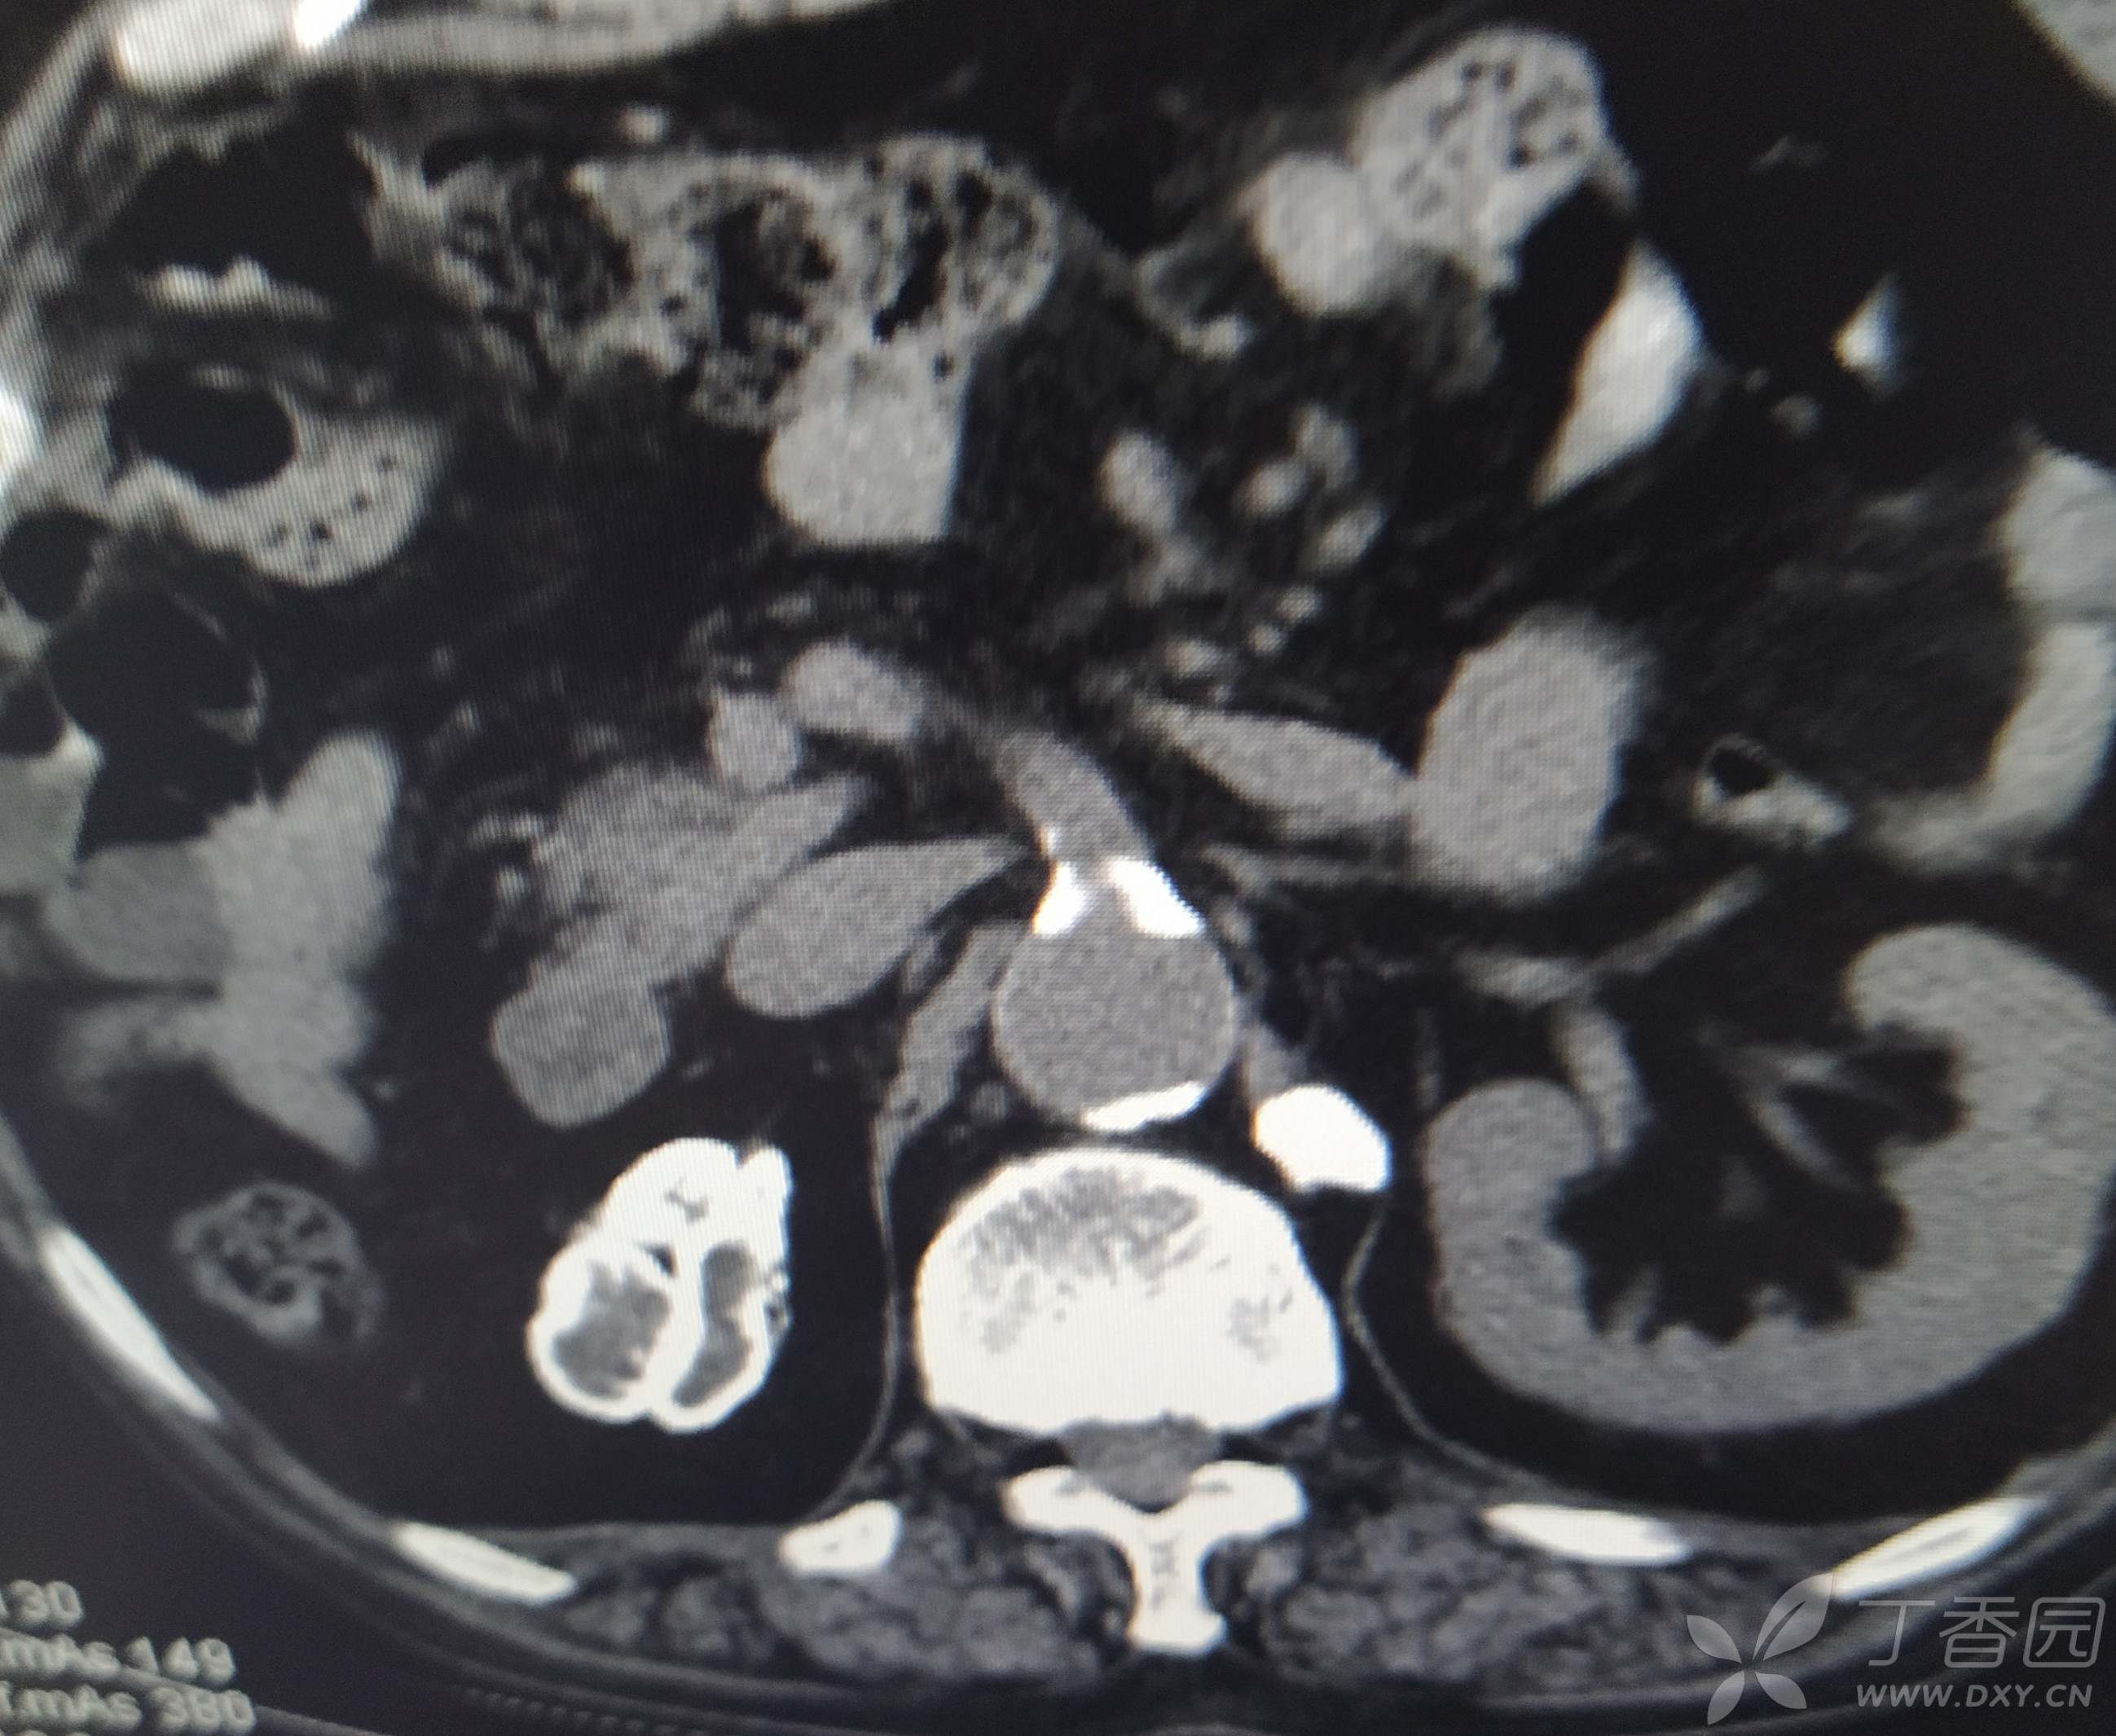

男,80岁,体检发现右肾呈坏死性钙化,肾周边钙化伴声衰减,CT可见明显钙化